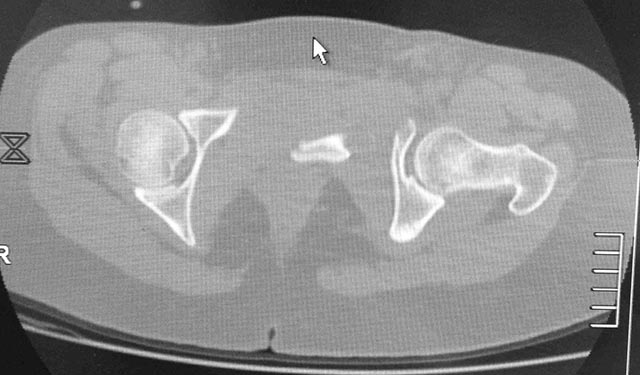

повреждение таза с необычным смещением |

Женщина,21, социальна, без вредных превычек, сбита авто.

Кожа не повреждена. Других повреждений нет. Гемодинамически стабильна. травме 2 сут. Планируем спереди открыто через Stoppa, далее сзади крестец и ость закрыто (крестец может через обе массы?). Интересует мнение по альтернативным вариантам и по предложенному (tricks and shots). Заранее благодарен.

PS Только часть скринов с body scan, один с контрастированием пузыря.